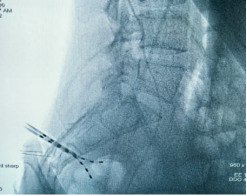

2026年1月30日,完善术前准备后,手术于全麻并全程电生理监测下进行,历经5小时苦战,顺利于腰膨大处置入外科电极一枚,双侧骶3孔各植入一根穿刺电极,连接2枚刺激器后埋置于皮下。手术实施顺利,术中X线检查植入位置良好。目前患者生命体征平稳,已开机测试,后期动态调整刺激参数,并结合非侵入式脑机接口锻炼。

成功植入565外科电极

双侧骶3孔顺利植入穿刺电极